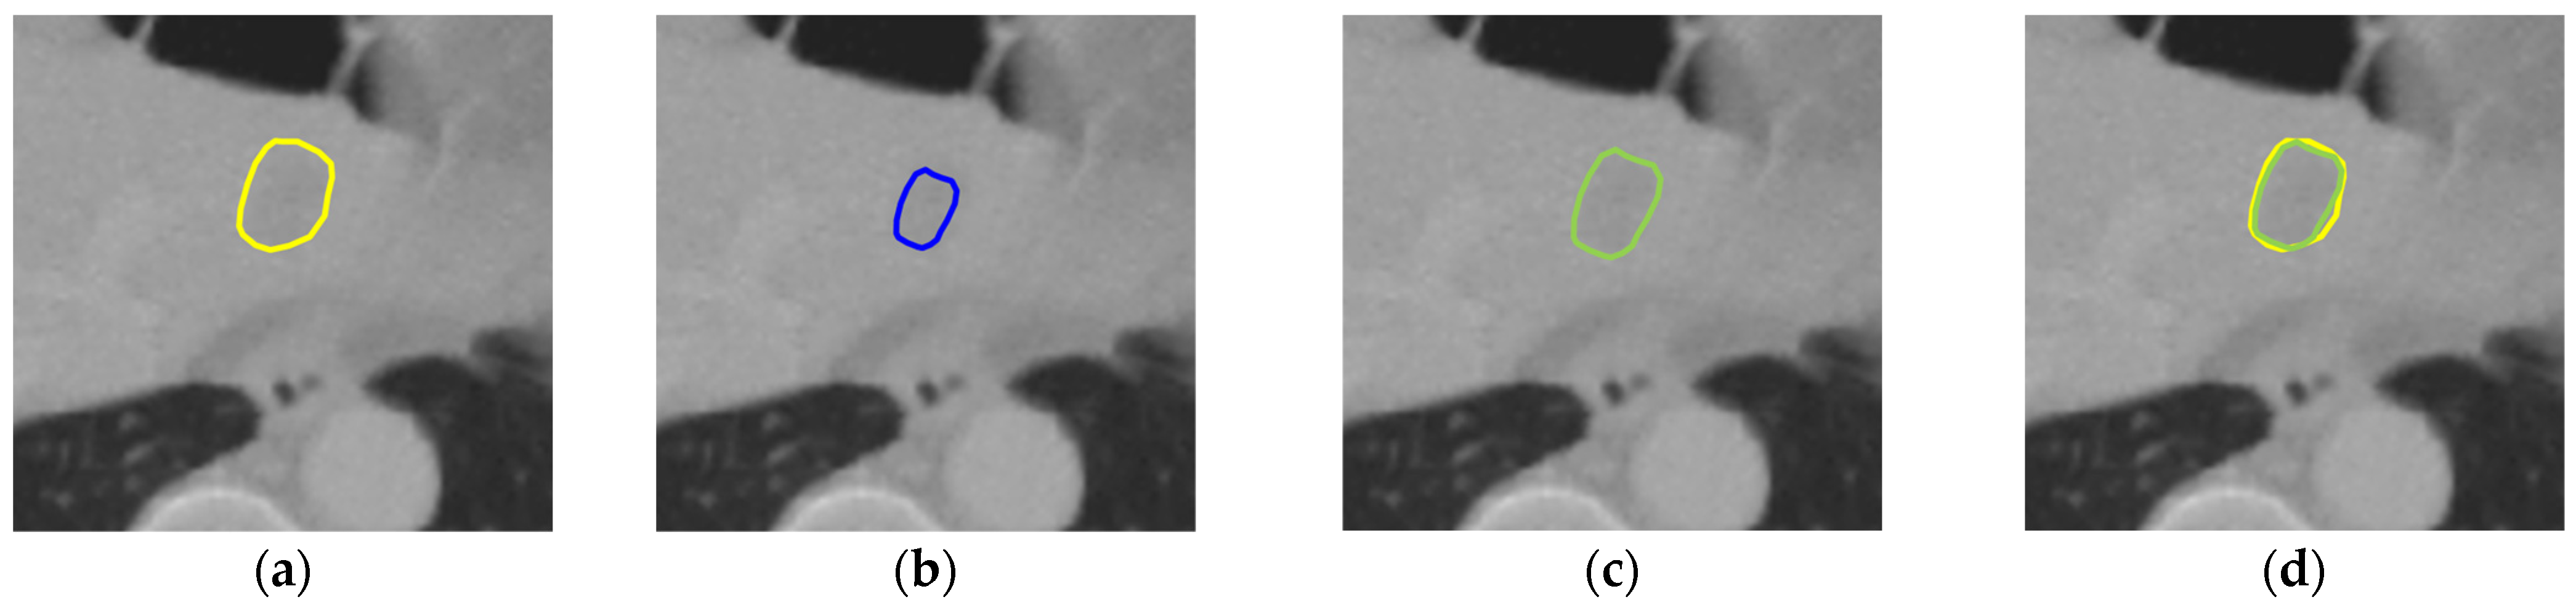

To determine the right number of times of the morphological dilation operation in our post-processing method, we applied the morphological dilation operation from one to three times to compare their performance. As shown in Table 3, for the LiTS dataset, the best performance was achieved with the one-time application of the dilation operation, but the differences with the two-time application and the three-time application were small, whereas for the 3DIRCADb dataset, the results showed that applying dilation twice resulted in the best performance in terms of all evaluation metrics. Therefore, the post-processing method that applies the morphological dilation twice was adopted for our liver tumor segmentation method. As shown in Figure 6, after post-processing, the dilated tumor boundary is closer to the ground truth tumor boundary.

Figure 6. An illustration of the post-processing result: (a) the ground truth tumor boundary (yellow); (b) the predicted tumor boundary before post-processing (blue); (c) the dilated tumor boundary after post-processing (green); (d) the overlay of the ground truth tumor boundary (yellow) and the dilated tumor boundary (green).